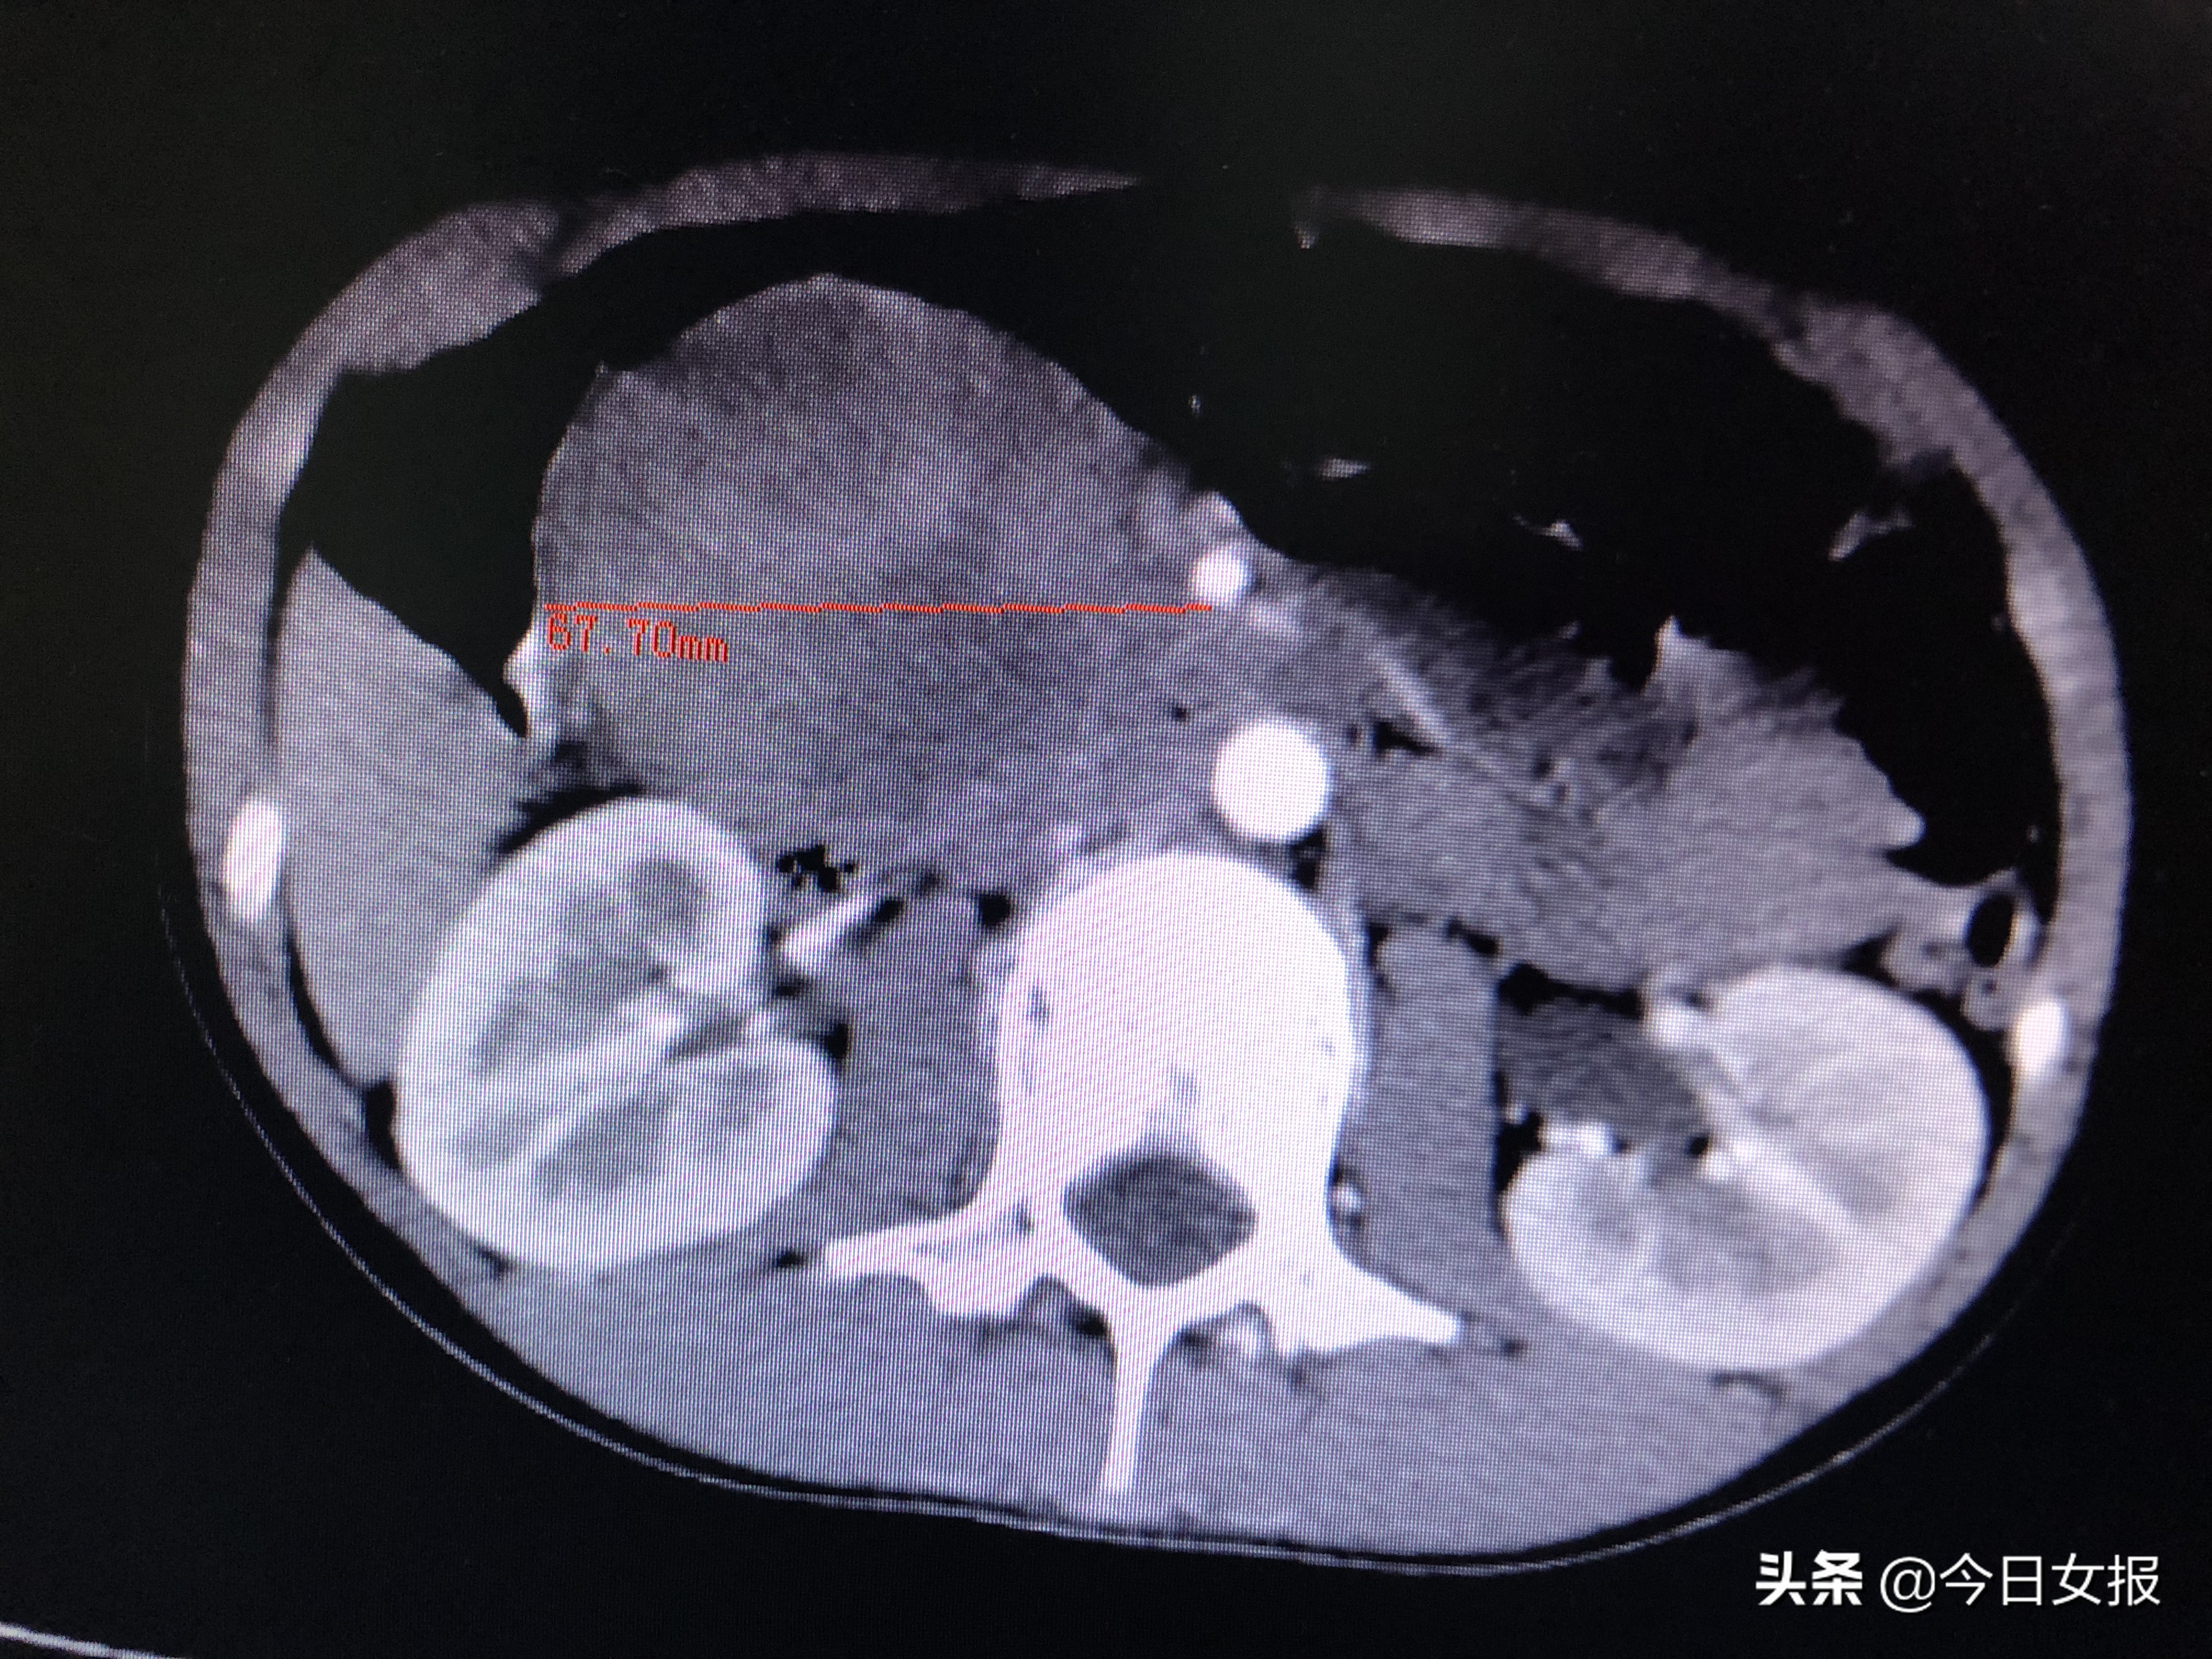

4月17日晚上7时许,在完善相关检查进一步明确病情并排除手术禁忌后,由蒋波、陈梅福、成伟等专家组成的手术团队为婷婷施行急诊全麻下腹腔镜胰十二指肠切除术。术中发现,肿瘤压迫十二指肠、结肠,且出血后粘连严重,腹腔镜下分离难度极大;同时,肿瘤与肠系膜上静脉、肠系膜上动脉、门静脉等重要血管紧邻,一不谨慎就容易损伤这些大血管,手术风险和难度不言而喻。所幸在专家团队的高超技艺和谨慎操作下,手术于次日清晨3时许顺利结束,切下的肿瘤达67×61×50mm3,病理检查证实为“胰头实性假乳头状瘤并出血”。